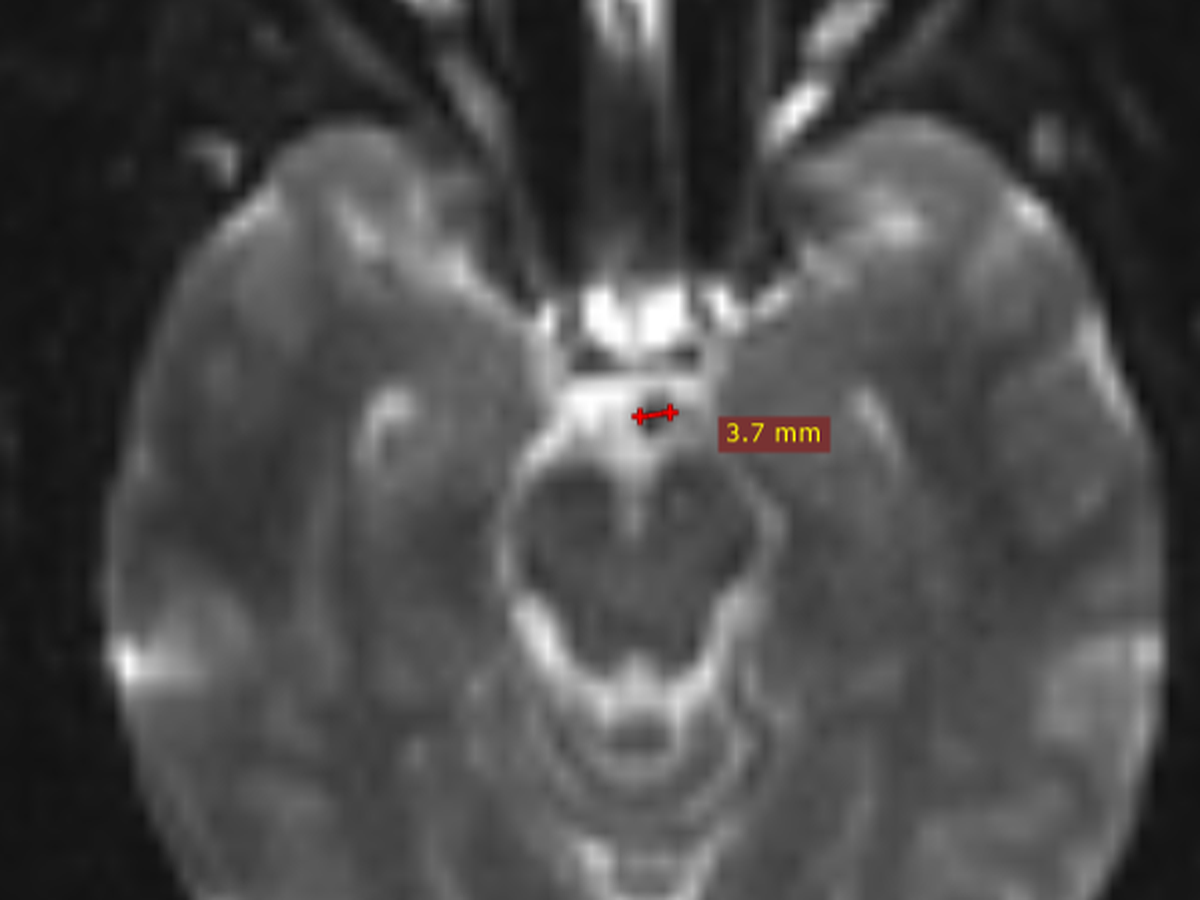

Join us in supporting Carrie Marcum, a resilient woman who has faced a challenging health journey. Carrie was diagnosed with a CSF (Cerebrospinal Fluid) Leak, a condition that causes fluid to leak from around her brain; spinal fluid sac. Unfortunately, her symptoms were initially overlooked, leaving her desperate for proper medical attention for more than 1/3 of a year.